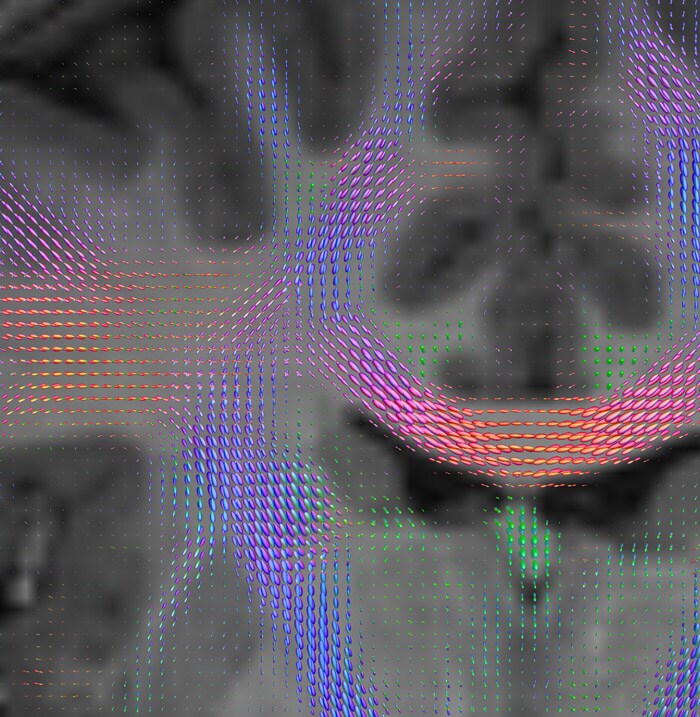

Fiber tractography of the corticospinal tract with seed region of the posterior limb of the internal capsule. Different processing based on the same data.

All images were created from the same acquisition in a child using Ingenia 3.0T CX and 32-channel dS Head coil. Diffusion data was acquired at b-values 0, 500, 1000, 2000, 3000. The use of high b-values (3000 s/mm2) effectively suppresses extra-axonal water signal and provides high angular resolution.

CSD of multishell DWI results in the white matter FOD at each voxel. Unlike the conventional diffusion tensor model, this approach enables accurate modeling of multiple fiber populations within a single voxel.

Crossings of the corpus callosum, corticospinal tracts, and the superior longitudinal fasciculus are shown.